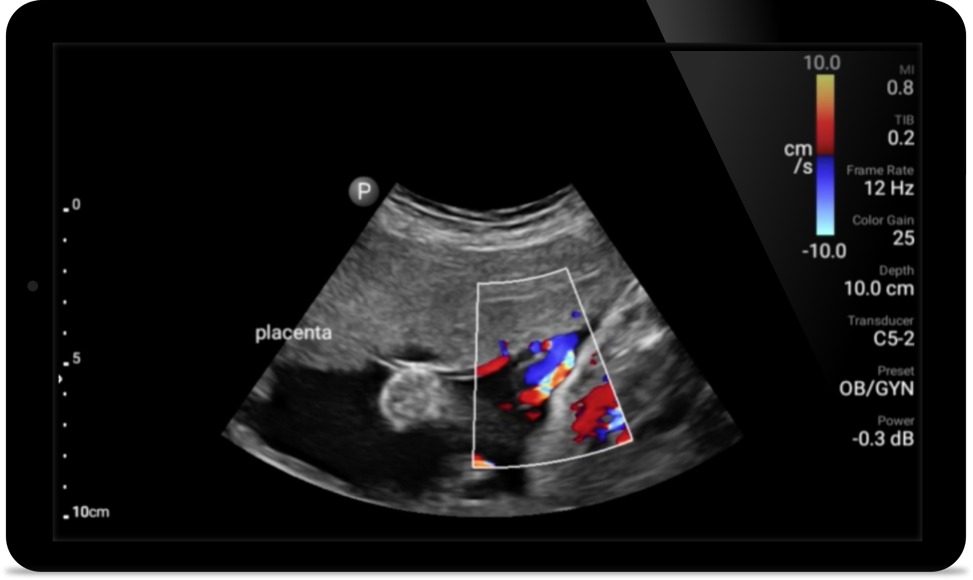

Lumify C5-2 broadband curved array transducer

• 5 to 2 MHz extended operating frequency range • 50mm radius of curvature • 2D, color Doppler, M-mode, advanced XRES and multivariate harmonic imaging, SonoCT • High-resolution imaging for deeper applications: abdominal, gall bladder, OB/GYN and lung imaging preset optimizations